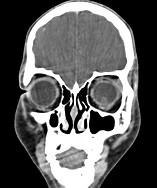

问题 女性,46岁,自述左眼视物不清约3个月,CT扫描如图所示,请选择正确的描述或答案 ( )

选项 A、考虑视网膜脱离 B、考虑玻璃体内出血 C、左侧玻璃体内偏后方见絮状高密度影 D、双侧眼环形态密度正常 E、双侧眼球未见病变

答案 C